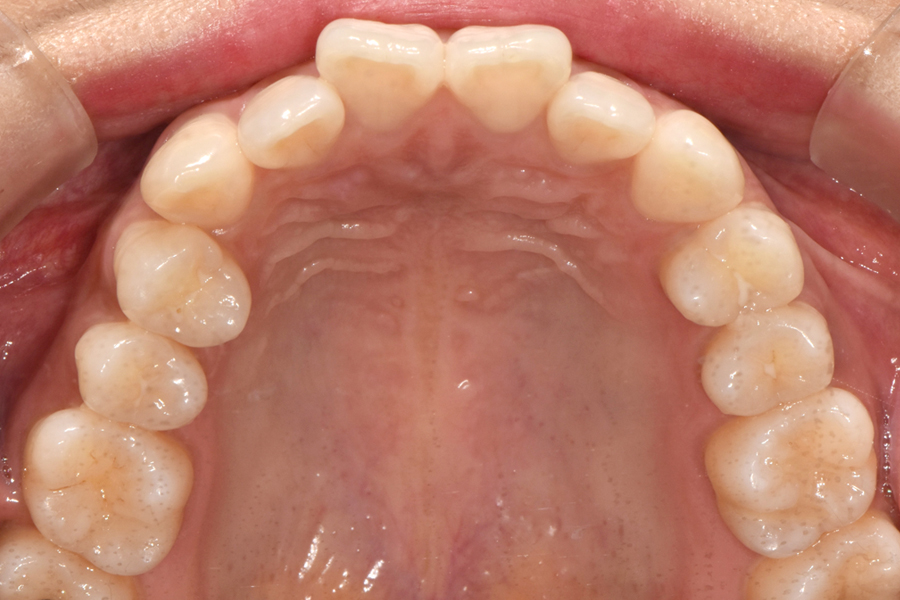

윗니를 보시면 치아 위치가 많이 틀어진 것을 볼 수 있는데요. 아래쪽 같은 경우 비교적 윗니보다 낫지만 그래도 한 쪽 치아가 좀 많이 튀어나와 있고 전체적인 악궁 형태가 조금 찌그러져 있는 것을 볼 수 있습니다.